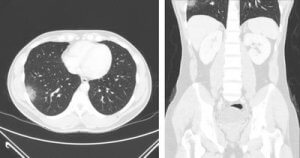

Як комп’ютерна томографія використовується в кардіології

Комп'ютерна томографія (КТ) зробила революцію в галузі кардіології, забезпечивши неінвазивний і точний спосіб діагностики та моніторингу серцевих захворювань. У цій статті ми розглянемо різні способи